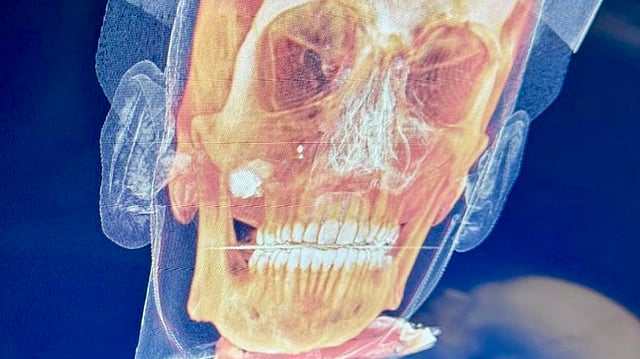

A medical scan of the victim  Gurpreet Sahota

A landscaper working outside was struck in the face by a bullet. As of November 16—eight days later—the bullet remained lodged, with the victim still awaiting surgical removal amid strains on British Columbia's healthcare system.

"More than a week has passed, yet the bullet lodged near his nose and jaw still hasn’t been removed," said journalist Gurpreet S. Sahota.